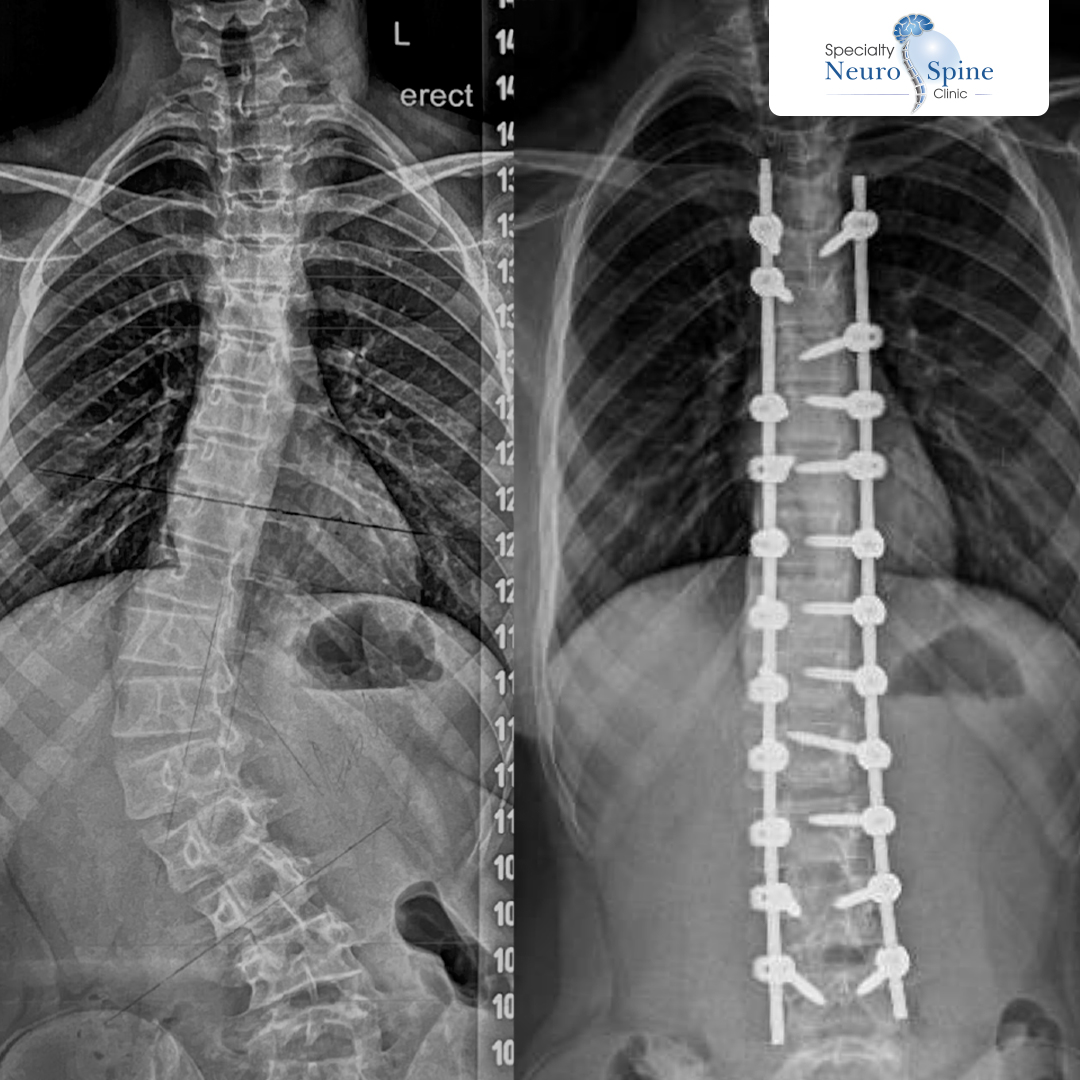

We were honored to welcome the lovely Maram, a 13 year old girl from Iraq. Dr. Firas Husban performed a minimally invasive spine surgery to correct her spinal curvature (scoliosis), spanning from the fourth thoracic vertebra (T4) to the fourth lumbar vertebra (L4).

Before-and-after X-rays.

Dr. Firas Husban performed a successful minimally invasive spinal correction surgery, addressing a spinal curvature from the fourth thoracic vertebra (T4) to the fourth lumbar vertebra (L4).